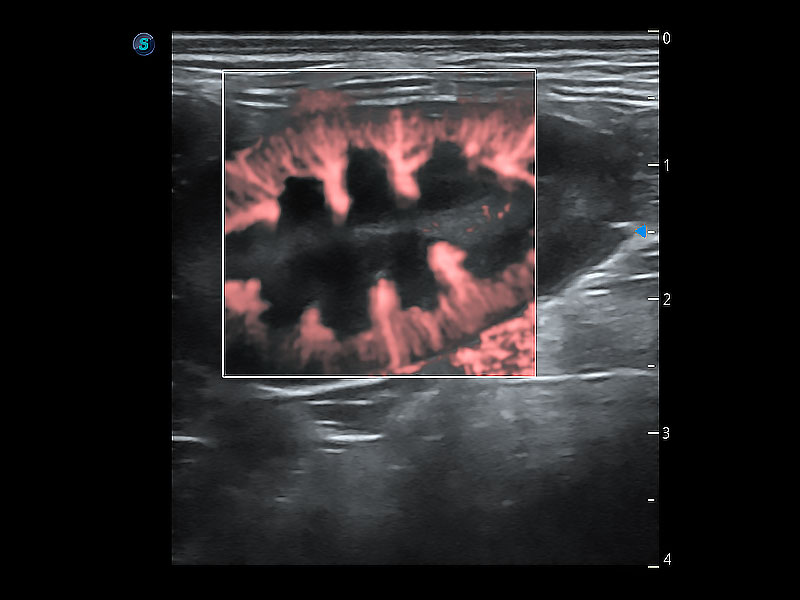

实时用颜色表示心肌组织运动,观察和定量组织的运动情況,对快速检测与评估心肌的灌注和活性、电传导及心肌收缩和舒张功能等均能提供重要的诊断信息。

能够增加心肌组织与血流之间的区别。对于心脏扫查困难的动物,可提供更好的心内膜边界的显示。